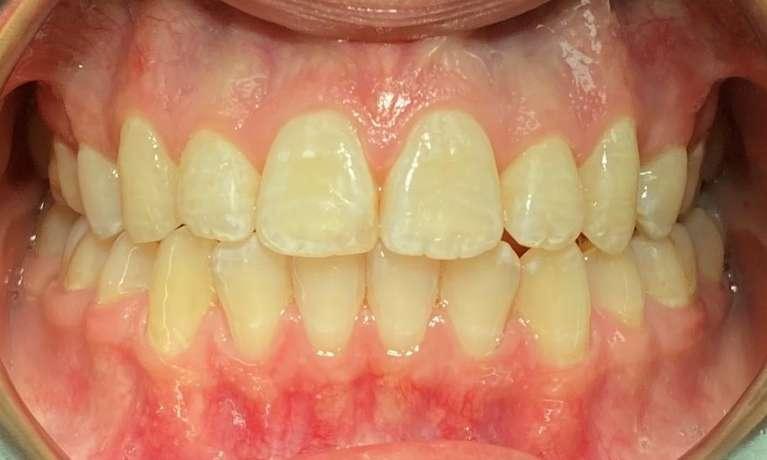

This patient had worn down her teeth over the years due to a bad bite. Dr. Farahani used Invisalign to move the teeth into a position where they could be restored and then placed 4 crowns top and bottom to give her back the length of her front teeth. This is a great example of the conservative restorative care provided at Harmony Dental Wellness to bring your mouth and body back into balance!